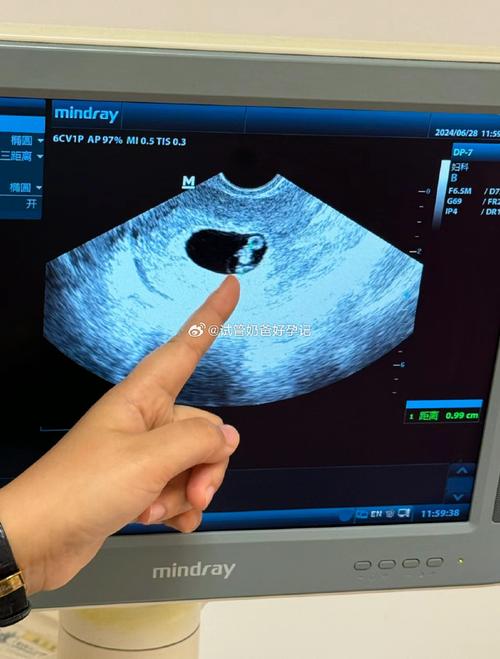

宫外孕就是受精卵在子宫体腔以外的部位着床发育,最常见的就是输卵管妊娠。这就好比一颗种子,没在该生长的肥沃土地里扎根,却跑到了别的地方,这肯定长不好啊。一旦发生宫外孕,不仅宝宝保不住,对妈妈的身体伤害也特别大。有些女性经历了宫外孕后,输卵管受损,自然受孕变得十分困难,甚至可能就失去了做妈妈的机会,这对一个家庭来说,打击实在是太大了。 这时候,试管婴儿技术就像是黑暗中的一道光,给这些家庭带来了希望。试管婴儿可不是在试管里长大的宝宝哦,简单来说,它是把卵子和精子都取出来,让它们在体外的实验室环境里自然结合或者通过技术手段结合形成受精卵,然后再把发育好的胚胎移植到妈妈的子宫里,让它在子宫里着床、发育。 在天门,就有不少家庭受益于这项技术。我认识一对夫妻,小王和小李。他俩结婚后一直盼着能有个孩子,可备孕了好久都没动静。后来好不容易怀上了,结果却是宫外孕,做了手术切除了一侧输卵管。这之后,他们又努力了很久,还是没能再次怀孕。看着身边的朋友都有了自己的宝宝,小王心里别提多着急了,晚上常常睡不着觉。后来听人介绍,他们来到了天门一家专业的生殖医院,选择了试管婴儿技术。 医院的医生们非常专业,先是对小王和小李进行了全面的身体检查,了解他们的身体状况后,为他们制定了个性化的治疗方案。经过一系列的准备工作,取卵、取精、胚胎培养,终于成功培育出了优质的胚胎。当胚胎被移植到小王子宫里的那一刻,他们既紧张又期待。经过漫长的等待,验孕结果出来了,小王成功怀孕了!那一刻,夫妻俩激动得热泪盈眶。后来,小王顺利生下了一个健康可爱的女宝宝,一家人别提多高兴了。 试管婴儿技术的成功离不开背后专业的医疗团队和先进的设备。在天门的这些生殖医院里,医生们都是经过多年专业学习和丰富临床经验积累的。他们就像一群守护生命的天使,用自己的知识和技能,为每一个家庭努力。而且,医院不断引进国际先进的设备,从取卵、胚胎培养到移植等各个环节,都有高精度的仪器保驾护航,大大提高了试管婴儿的成功率。 当然啦,试管婴儿也不是百分百能成功的。它的成功率受到很多因素的影响,像女性的年龄、身体状况、子宫环境,还有胚胎的质量等等。